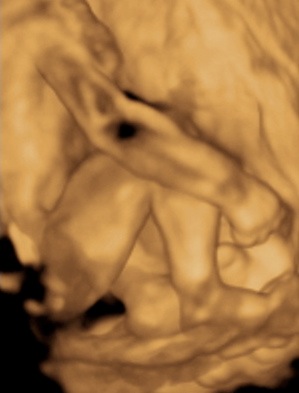

A 3D-s babafotok meg mindig lenyugoznek, nem birok betelni veluk. SZomoruan olvasom, hogy mennyi aprobb-nagyobb kellemetlensegetek van, de szerintem mindenki nagyon szuperul halad, ugyesek vagytok...le a kalappal foleg a dolgozok, vagy mar babasok elott! majd most teszek fel kepeket es is Azzurrarol, bar mar tobb, mint 5 hete keszultek, de ujabbak mar nem lesznek, es mivel kimaradtam abban az idoszakban, most potolom. Az tuti, hogy ezentul mindenkinek javasolni fogom a 4D-t ilyen koran is (22+1 hetesen voltunk), mert bar csimota ducibb volt az atlagnal es mar akkor volt rajta jo adagnyi izom (ez is a napi 1 l tej

), de egy sovanyabb baba is csodaszep szerintem...mindent el lehet mondani, csak azt nem, hogy csontkollekciok lennenek. Osszessegeben ugy nez ki, hogy ram hasonlit, de a szemoldokcsontja es a szaja az egy az egyben a parome...szerencsere...neki az sokkal szebb...remelem, haj-ugyben is ra ut majd